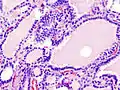

Hyperthyroidism is one of the most common endocrine conditions affecting older domesticated housecats. In the United States, up to 10% of cats over ten years old have hyperthyroidism.[60] The disease has become significantly more common since the first reports of feline hyperthyroidism in the 1970s. The most common cause of hyperthyroidism in cats is the presence of benign tumors called adenomas. 98% of cases are caused by the presence of an adenoma,[61] but the reason these cats develop such tumors continues to be studied.

The most common presenting symptoms are: rapid weight loss, tachycardia (rapid heart rate), vomiting, diarrhea, increased consumption of fluids (polydipsia), increased appetite (polyphagia), and increased urine production (polyuria). Other symptoms include hyperactivity, possible aggression, an unkempt appearance, and large, thick claws. Heart murmurs and a gallop rhythm can develop due to secondary hypertrophic cardiomyopathy. About 70% of affected cats also have enlarged thyroid glands (goiter). 10% of cats exhibit "apathetic hyperthyroidism", which is characterized by anorexia and lethargy.[62]